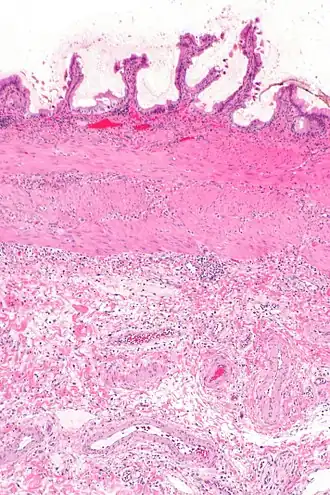

La cholécystite est l'inflammation de la vésicule biliaire.

La cholécystite est liée à l'infection du liquide vésiculaire, suite le plus souvent à l'obstruction du canal cystique par un calcul biliaire : le liquide en stase, d'abord stérile, provoque une inflammation locale qui peut se surinfecter alors, le plus souvent avec des germes digestifs présents dans le duodénum. Si elle n'est pas prise en charge convenablement, la vésicule biliaire peut se gangréner et provoquer une péritonite.

L'échographie hépatique montre une lithiase avec un aspect de cône d'ombre. Il existe un épaississement de la paroi de la vésicule biliaire, qui peut prendre un aspect feuilleté. La sonde d'échographie, passant au niveau de la vésicule, provoque la douleur (on parle donc de « Murphy échographique »). Ces signes sont très sensibles et spécifiques[4]. C'est l'examen fait en première intention.